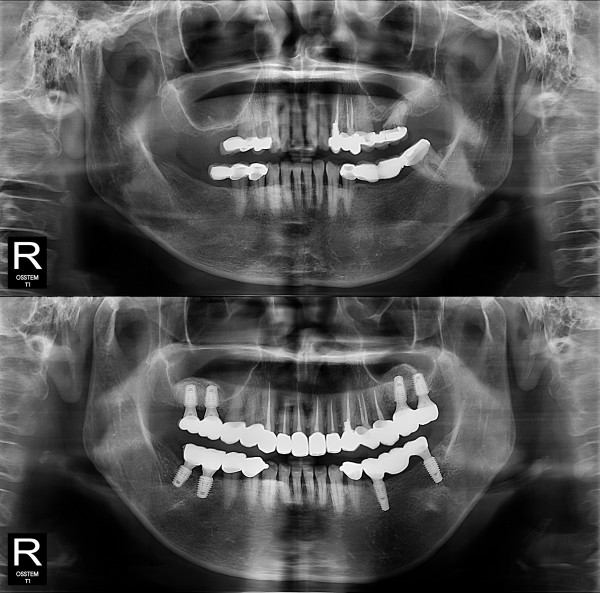

임플란트

부분 임플란트